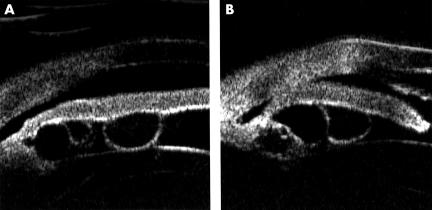

Figure 1.

Cross sectional appearance of the iris by ultrasound biomicroscopy in case 1. Multiple iridociliary cysts are seen in the posterior iris of both eyes: (A) 1.2 mm diameter cyst in the right eye; (B) 0.8 mm diameter cyst in the left eye.